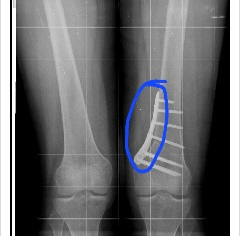

평소에 일을 나눠서 하던 두 다리가 수술 이후가 한 다리 혼자 모든 무게를 지탱하며 일을 해서 무리가 되는 상황입니다.

목발을 사용하지 않는 쪽의 다리에 추가적인 스트레스가 가해질 수 있습니다. 특히 체중이 100킬로그램이 넘는다면, 목발을 사용하는 동안 비수술 다리에 더 많은 체중이 실리게 되어 근육이나 관절에 무리가 갈 수 있습니다.